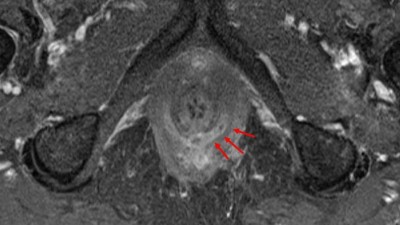

Für die Therapie von Analfisteln bei Morbus Crohn gibt es neue Methoden: allogene mesenchymale Stammzellen als Alternative zu expandierten Stammzellen aus Fettgewebe oder die bioaktive Matrix.

Hamburg/© FotografieLink / Getty Images / iStock, Vorbereitung für Koloskopie/© Eugene Nekrasov / Getty Images / iStock (Symbolbild mit Fotomodellen), Magenausgangsstenose/© SpringerMedizin.de, Frau hält sich die Hände vor den Bauch/© Tharakorn / Getty Images / iStock (Symbolbild mit Fotomodell), Colitis ulcerosa/© Springer Medizin Verlag GmbH, Transsphinktäre Fistel/© Springer Medizin Verlag GmbH, SARS-CoV-2 im Elektronenmikroskop, coloriert/© narvikk / Getty Images / iStock, Perianale Affenpocken-Infektion/© D. Sterzing / all rights reserved Springer Medizin Verlag GmbH, DGVS Logo/© Deutsche Gesellschaft für Gastroenterologie, Verdauungs- und Stoffwechselkrankheiten, Hamburg/© carol_anne / Stock.adobe.com, Leipzig/© Jakob Fischer / stock.adobe.com, Logo DGVS Kongress 2020/© RiverNorthPhotography / Getty Images / iStock